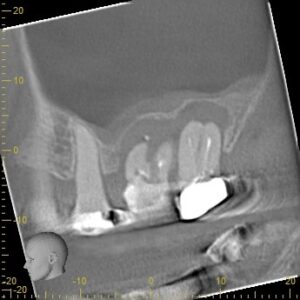

診断の正確さ:パーフォレーションの位置と大きさを特定する

東京(江戸川区小岩)の根管治療専門外来|笠原デンタルオフィスで、パーフォレーション(穿孔)」は根管治療の失敗!?原因と症状、対処法について解説

修復の第一歩は、穴の正確な情報を把握することです。

肉眼や通常のレントゲンだけでは、根管の影に隠れて穴の位置を正確に特定することはできません。

歯科用CBCT(3次元レントゲン)

通常のレントゲンでは判別できない、穿孔部位と周囲の骨との位置関係、感染の広がりを立体的に解析します。

これにより、修復材を詰める深さや方向を正確に計画できます。